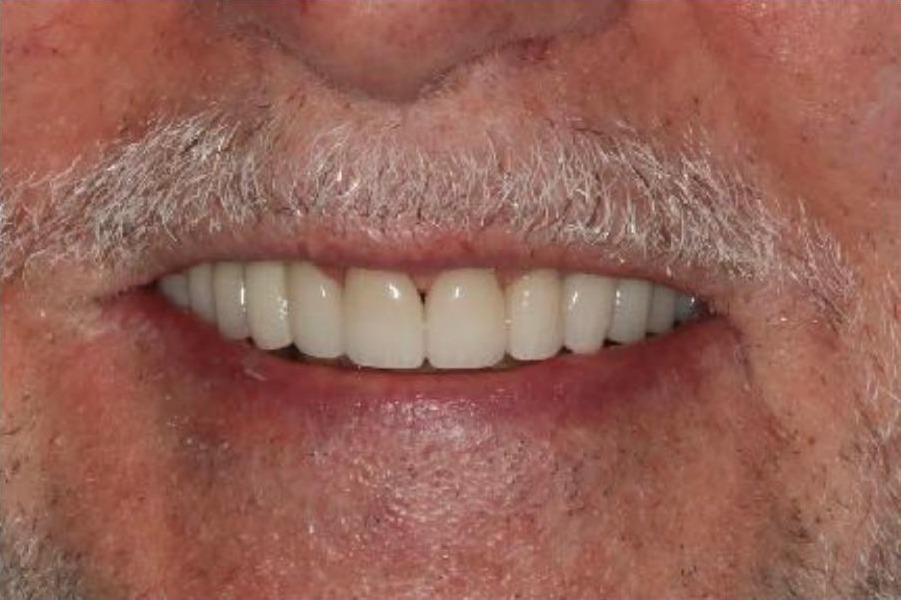

To improve this patient's dental health, esthetics and function, upper and lower implants were placed. I then fabricated an upper screw-retained implant bridge and a lower Overdenture, giving this patient back his smile and function. The patient was thrilled with the result and exclaimed "It looks good! I'll have all the women chasing me! I'd marry me if I wasn't already married!"

To improve this patient's dental health, esthetics and function, upper and lower implants were placed. I then fabricated an upper screw-retained implant bridge and a lower Overdenture, giving this patient back his smile and function. The patient was thrilled with the result and exclaimed "It looks good! I'll have all the women chasing me! I'd marry me if I wasn't already married!"